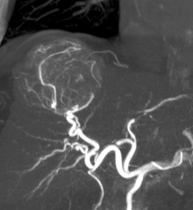

Module 6: Interventional Radiology

Module coordinator : Prof. Jean-Pierre Tasu

Indications for radiology treatments of hepatic tumors in cirrhotic patients- Indications for radiology treatments of liver metastases

- Indications and follow-up of radiology treatments for portal hypertension and portal vein thrombosis

- Role of interventional imaging in abdominal trauma

- Indications and follow-up of interventional radiology treatments for biliary and pancreatic diseases

- Interventional radiology and hepatic surgery: how to support the surgeon

- Post-SIRT and post-CEL imaging

- Indications for treatment of necrotizing acute pancreatitis

- Imaging of endoscopic treatments and combined therapies